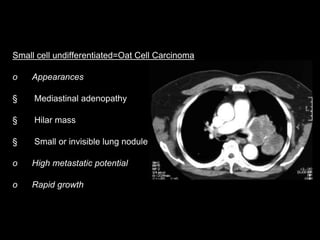

Small cell undifferentiated=Oat Cell Carcinoma

o Appearances

§ Mediastinal adenopathy

§ Hilar mass

§ Small or invisible lung nodule

o High metastatic potential

o Rapid growth